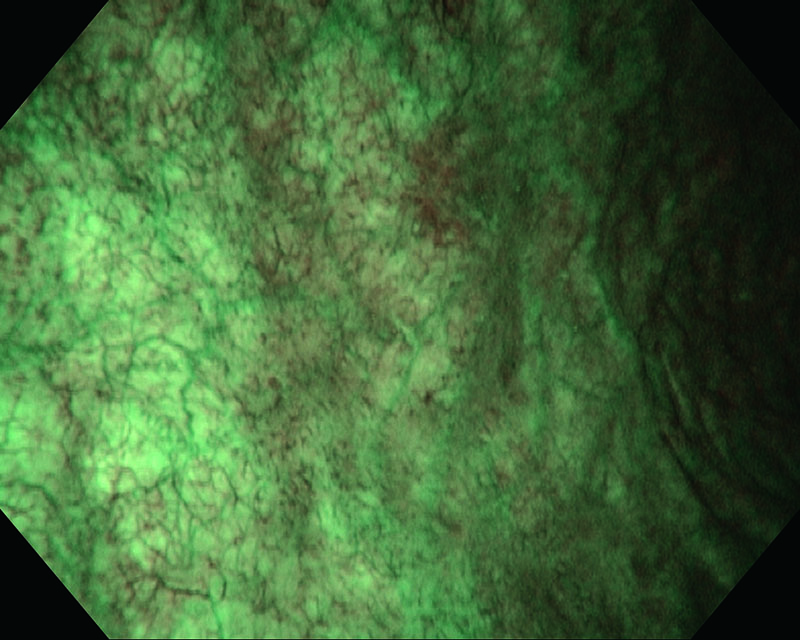

Rubor mucosa, 81 años, hombre

Luz blanca

NBI

Histología UC, CIS

Comentarios

El caso sospechaba carcinoma in situ e identificaba un rubor en la mucosa de la vejiga. El examen histopatológico reveló CIS.